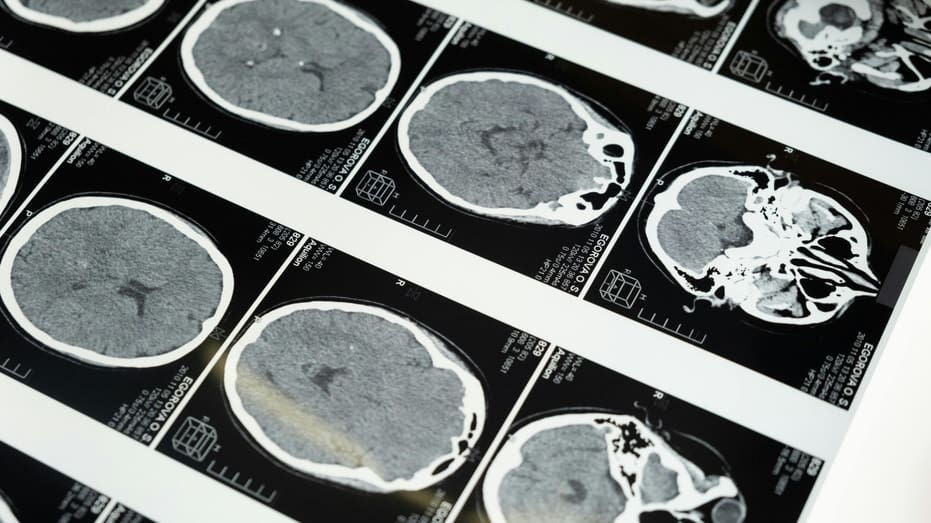

When you hear “brain-computer interface,” you probably picture surgery, wires and a chip in your head. Now picture something quieter. No implant. No incision. Just sound waves directed at the brain.

Most brain-computer interface systems rely on electrodes that detect electrical signals from neurons. Neuralink is the most visible example. It places tiny threads inside the brain to record activity. Ultrasound works differently.

Focused ultrasound treatments are already approved for Parkinson’s disease, uterine fibroids and certain tumors. That clinical history gives companies like Gestala a foundation to build on. However, studying or interpreting brain signals with ultrasound is far more complex than delivering targeted stimulation.